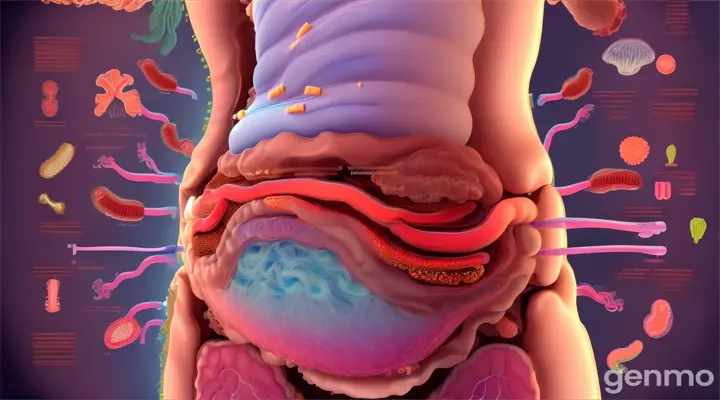

Prompt

blender